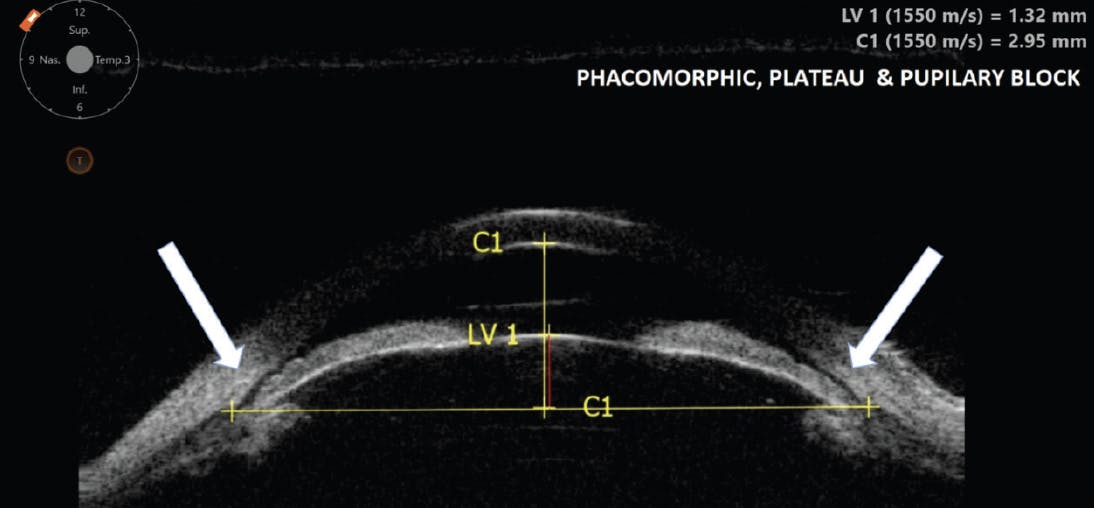

Plateau Iris configuration can present alone or be concomitant with a pupillary block or phacomorphic mechanism. Additionally, Plateau Iris is not always unfavorable. In certain cases when it concurs with the phacomorphic mechanism or pupillary block, the insertion of the iris root away from the trabeculum saves the patient from angle closure (Figure 2).

Figure 2. Combination of three risk factors for angle closure: Phacomorphic, Plateau Iris, and pupillary block. In this case, the anterior insertion of the iris into the ciliary body prevents effective angle closure.